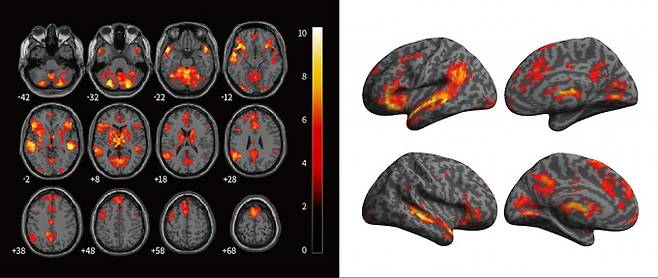

뇌 영상 연구는 사이버불링이 피해자에게 어떻게 신경학적 변화를 일으키는지 시각적으로 제시한다. 기능적 자기공명영상(fMRI) 연구에 따르면 사이버불링 피해자는 사회적 배제나 괴롭힘을 경험할 때 뇌의 전대상피질(dACC) 활동이 증가하는 경향을 보인다. (doi:10.1002/hbm.2489)

이 영역은 신체적 고통을 직접 경험할 때 활성화된다. 온라인에서 받는 악성 댓글과 모욕이 일시적, 감정적인 상처에서 그치지 않고 피해자의 뇌가 이 사이버불링을 실제 '고통'으로 받아들인다는 의미다.